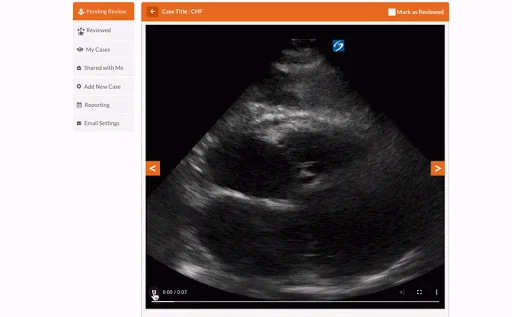

Upload & share your POCUS scans.

Track All Your Practice Scans in One Place

Becoming proficient at ultrasound requires hundreds of practice scans and access to POCUS experts to provide feedback on your scanning technique and interpretation. Our Scan Portfolio lets you have this vital experience while learning POCUS remotely!

Upload all your practice scans in one online portal that is accessed through the GUSI website. Track your credentialing hours and progress towards proficiency. Share your scans with your residency program faculty and GUSI instructors for direct feedback. You can also share scans with fellow residents and learn from their cases.